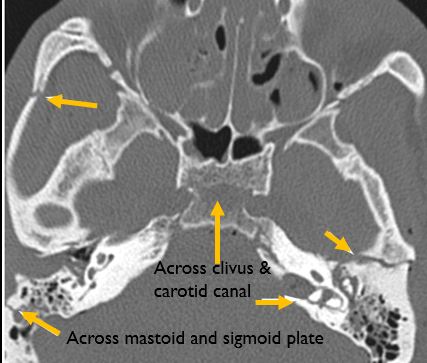

Central Skull Base and Calvarium

The roof of the mastoid and/or middle ear is fractured.